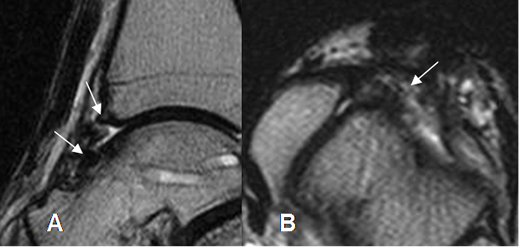

Con la RM se valora el grado de daño cartilaginoso (16). Además se aprecia el edema óseo y los signos de sinovitis en el receso capsular anterior. (15). (Fig 90, 91).

Fig 90. Pinzamiento anterior.

A: RM sagital en T2. Formación de osteofitos.

B: RM axial en T2. Derrame articular en la parte anterior de la articulación, con sinovitis asociada. (Flecha).